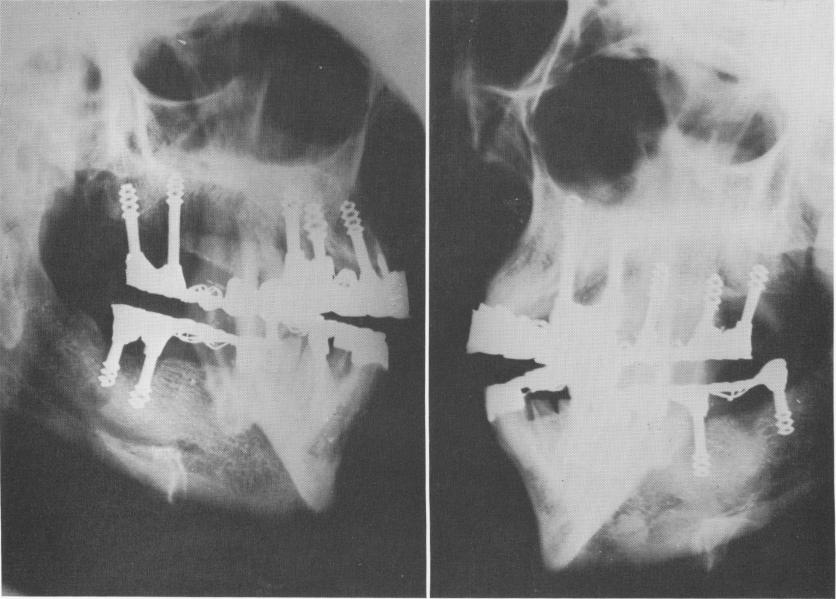

Fig. 4-19. Radiographs taken 3 years postoperatively. The implants are secure in bone and no pathologic areas are seen.

2 Xray of Chercheve`s spiral post implants in bone with no pathology